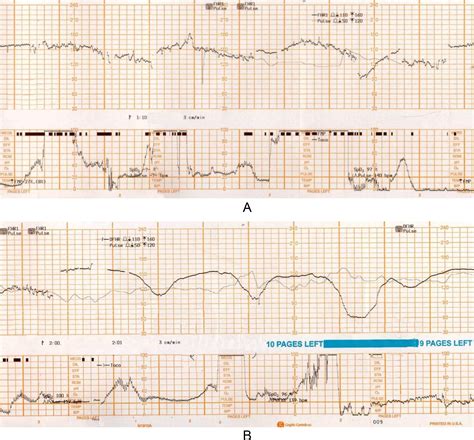

A Fetal Scalp Electrode is a specialized medical device used to monitor the fetal heart rate during labor. Unlike external monitors, which use ultrasound or Doppler technology, an FSE provides a direct electrical signal from the fetus's scalp. This direct measurement is more accurate and reliable, especially in situations where external monitoring is challenging due to factors like maternal obesity, fetal position, or excessive movement.

• Accurate Monitoring: FSE provides a direct and continuous measurement of the fetal heart rate, which is more accurate than external monitoring.

• Early Detection: It allows for early detection of any changes in the fetal heart rate, enabling timely intervention if necessary.

• Reduced Interference: Unlike external monitors, FSE is not affected by maternal movement or obesity, providing clearer and more reliable data.